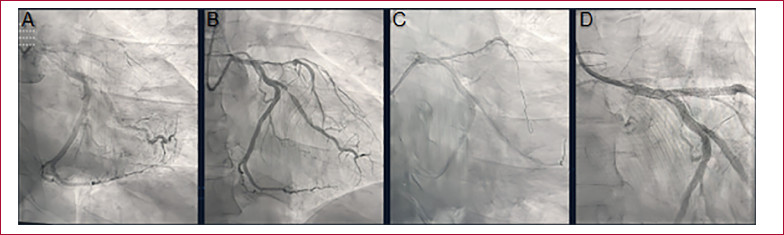

Cinecoronariografía (CCG). A. CCG de ingreso. B. CCG a las 24 horas del tratamiento con fibrinolíticos. C. Angioplastia de la lesión culpable, cuerda en la arteria descendente anterior. D. Resultado angiográfico final luego de la colocación de los stents.

Ingresa a las 22 h con persistencia del dolor precordial con ECG que presenta los cambios referidos (Figura 1). Se realiza cinecoronariografía por acceso radial izquierdo, con tiempo puerta aguja de 10 minutos. (Figura 2 A) Se observa la arteria descendente anterior ocluida desde el origen, con tenue opacificación del lecho distal a través de circulación homo y heterocoronariana. El ramo lateroventricular de la arteria circunfleja presenta una lesión del 80% a nivel del tercio proximal. La arteria coronaria derecha está ocluida en el tercio medio, y su lecho distal se opacifica a través de circulación colateral homocoronariana.

A las 24 horas del ingreso se realiza nueva cinecoronariografía que demuestra lesión ulcerada en el tronco de la arteria coronaria izquierda y la arteria descendente anterior permeable, con extensa lesión grave desde su origen hasta el tercio medio con flujo TIMI II. (Figura 2 B). El resto de las arterias no demuestran diferencias con respecto al cateterismo previo. En dicho procedimiento se logra realizar angioplastia de la arteria descendente anterior con colocación de dos stents liberadores de drogas, angioplastia del tronco de coronaria izquierda con un stent liberador de droga y angioplastia de la arteria circunfleja con dos stents liberadores de drogas.

El procedimiento se realiza por punción radial y sin complicaciones. (Figura 2 C y D).